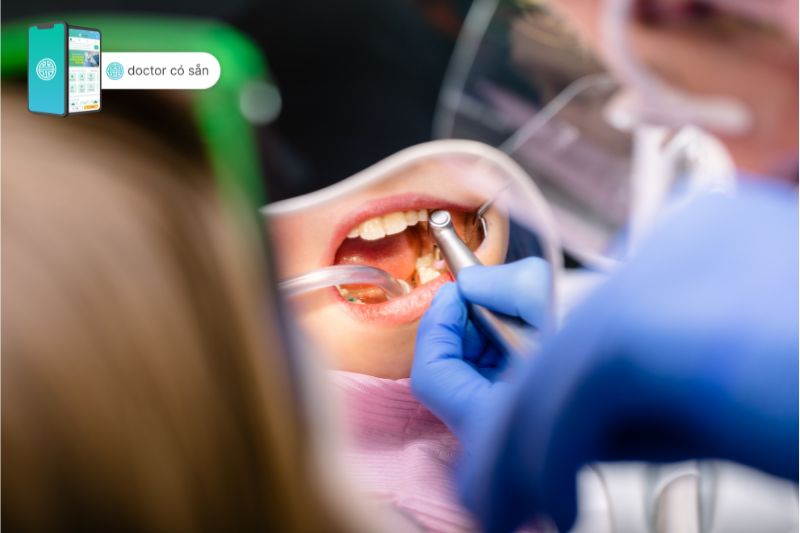

Quy trình thực hiện dán veneer răng sẽ được thực hiện lần lượt theo thứ tự như sau:

Lần thực hiện 1

- Nha sĩ sẽ khám tổng quát, tư vấn chọn lựa loại mặt dán veneer và số lượng cần dán để đạt thẩm mỹ tốt nhất. Nếu răng bị khuyết điểm nhiều như hô, móm, khấp khểnh nhiều thì cần phải niềng cho đều rồi mới dán veneer cho răng.

- Chụp X – quang để đánh giá sức khỏe răng. Nếu có sâu răng, bệnh nướu răng,… cần phải điều trị trước.

- Nha sĩ sẽ mài bớt khoảng 0,2 – 0,5mm mặt ngoài răng. Lớp men mài đi sẽ tương đương với độ dày mặt dán veneer.

- Nha sĩ sẽ lấy dấu bề mặt răng đã mài gửi đến labo để thực hiện dán veneer.

Lần thực hiện 2

- Trước khi dán veneer, nha sĩ sẽ kiểm tra độ vừa vặn, hình dạng, màu sắc của mặt dán.

- Nha sĩ sẽ làm vệ sinh răng thật kỹ để vi khuẩn không bị đọng dưới lớp veneer phát triển gây thối rữa mặt răng.

- Loại nhám mặt răng bằng gel chuyên dụng để giúp cho mặt dán veneer bám chặt vào răng hơn.

- Gắn mặt dán veneer lên răng, sử dụng xi măng nha khoa chuyên dụng để dán dính veneer với răng thật.

- Kiểm tra khớp cắn xem tương thích chưa, cuối cùng là đánh bóng mặt dán veneer hoàn tất.